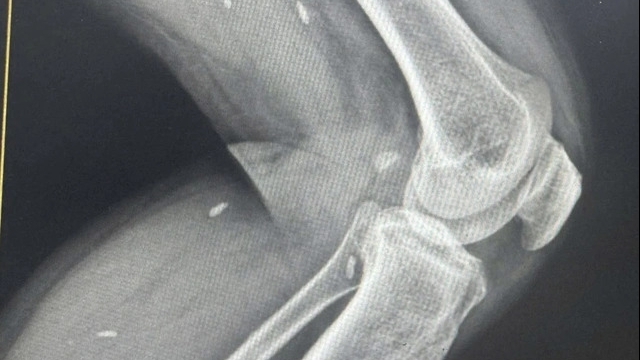

Bệnh nhân được đưa vào Bệnh viện Đa khoa Quảng Nam cấp cứu. Tiến hành nội soi, bác sĩ phát hiện hàm răng nằm sâu trong thực quản bệnh nhân, phía ngoài dị vật nhọn có khả năng đâm thủng thành thực quản.

Khi nội soi, bác sĩ Bệnh viện Đa khoa Quảng Nam phát hiện hàm răng nằm sâu trong thực quản bệnh nhân, góc nhọn của hàm có khả năng đâm thủng thành thực quản.

"Kíp bác sĩ đã nội soi gắp ra bộ răng giả dài khoảng 3 cm, rộng gần 2 cm", Trưởng khoa Tai mũi họng, bác sĩ Nguyễn Thanh Tiên cho biết.

| Răng giả được lấy ra ở thực quản người phụ nữ |